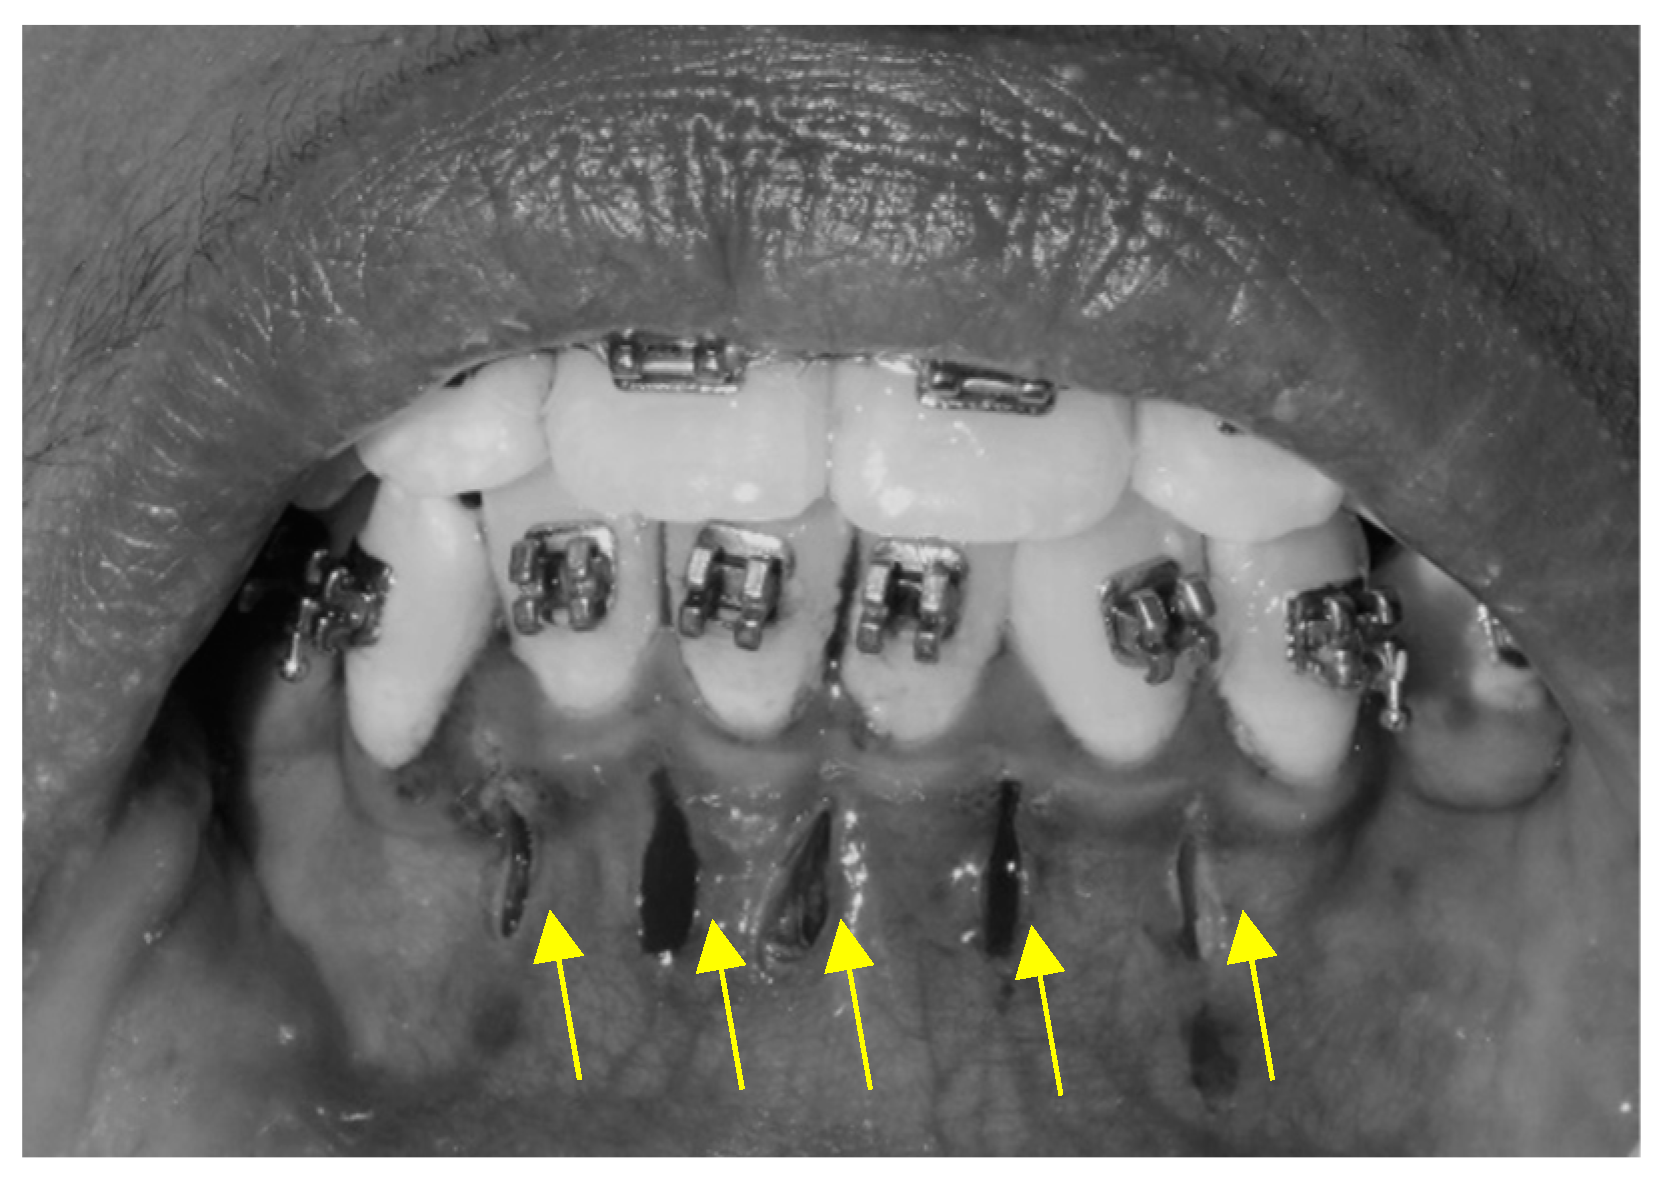

2.3.1. Piezocision Procedure (PZ)